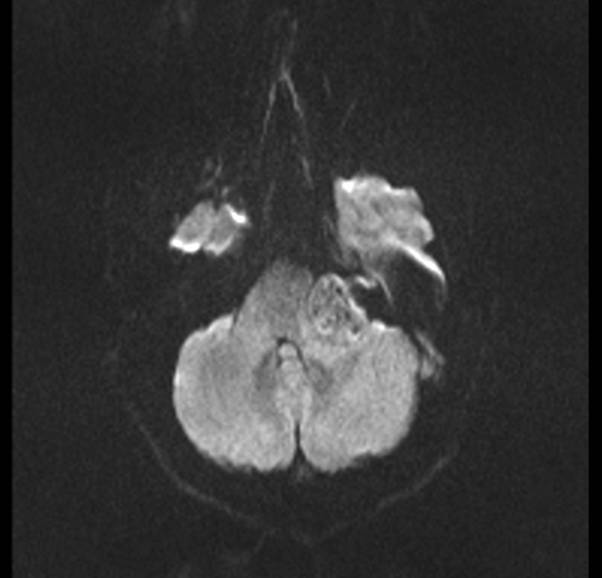

Paciente de 42 años, que ingresa para resección de posible schwanoma vestibular izquierdo